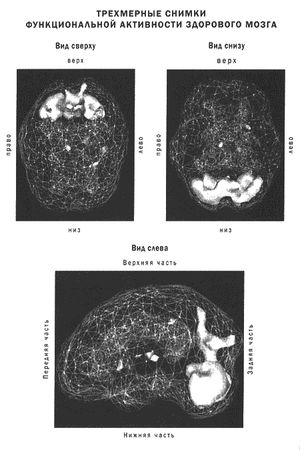

Второй тип снимков ОЭКТ, использованных в этой книге, - это трехмерные снимки функциональной активности мозга, где умеренная активность мозга сравнивается с верхними 15 % активности.

Такие снимки помогают выявить сверхактивные зоны мозга и полезны для диагностики припадков, обсессивно-компульсивного расстройства, тревожных нарушений и определенных форм депрессии.

Например, трехмерный скан активности здорового мозга обычно показывает повышенную активность (на иллюстрации - более светлый цвет) в задних отделах мозга (мозжечок, зрительная кора затылочных долей) и среднюю активность в остальных областях.